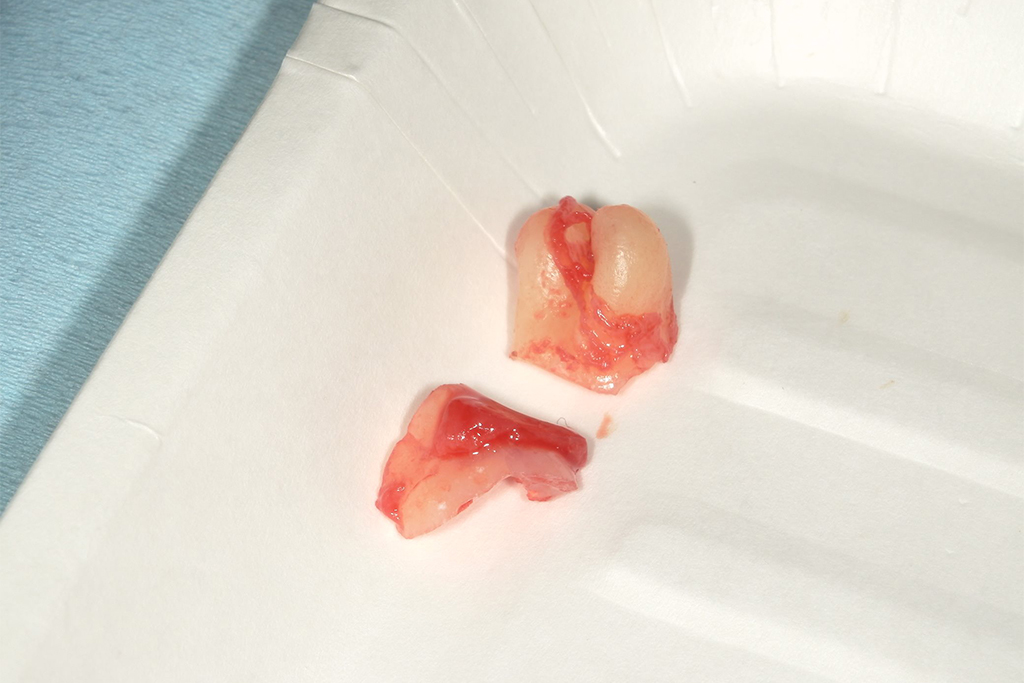

| 患者の年齢 | 30歳 |

|---|---|

| 症状 | 親知らずが痛い |

| 治療内容 | 親知らず抜歯1本 |

| 費用 | 約5,000円 (検査料、CT費、処置料、処方箋費用) |

| 治療期間 | 1日 |

| デメリット・ リスク |

麻痺が起こる場合がある、痛みが伴う |